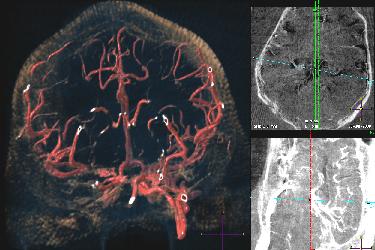

NECStR has been fully operational since May 3 2007 with a special focus is on image guided interventions for minimally invasive treatment of vascular disease. The center’s expertise and resources enable animal modeling of vascular pathologies, 3D x-ray imaging, post acquisition image processing, rapid prototyping from medical imaging and image guided minimally invasive surgery. Although the center’s focus lies in cardiovascular imaging and intervention, previous work has included selective vascular drug delivery for cancer treatment and orthopedic device implantation.